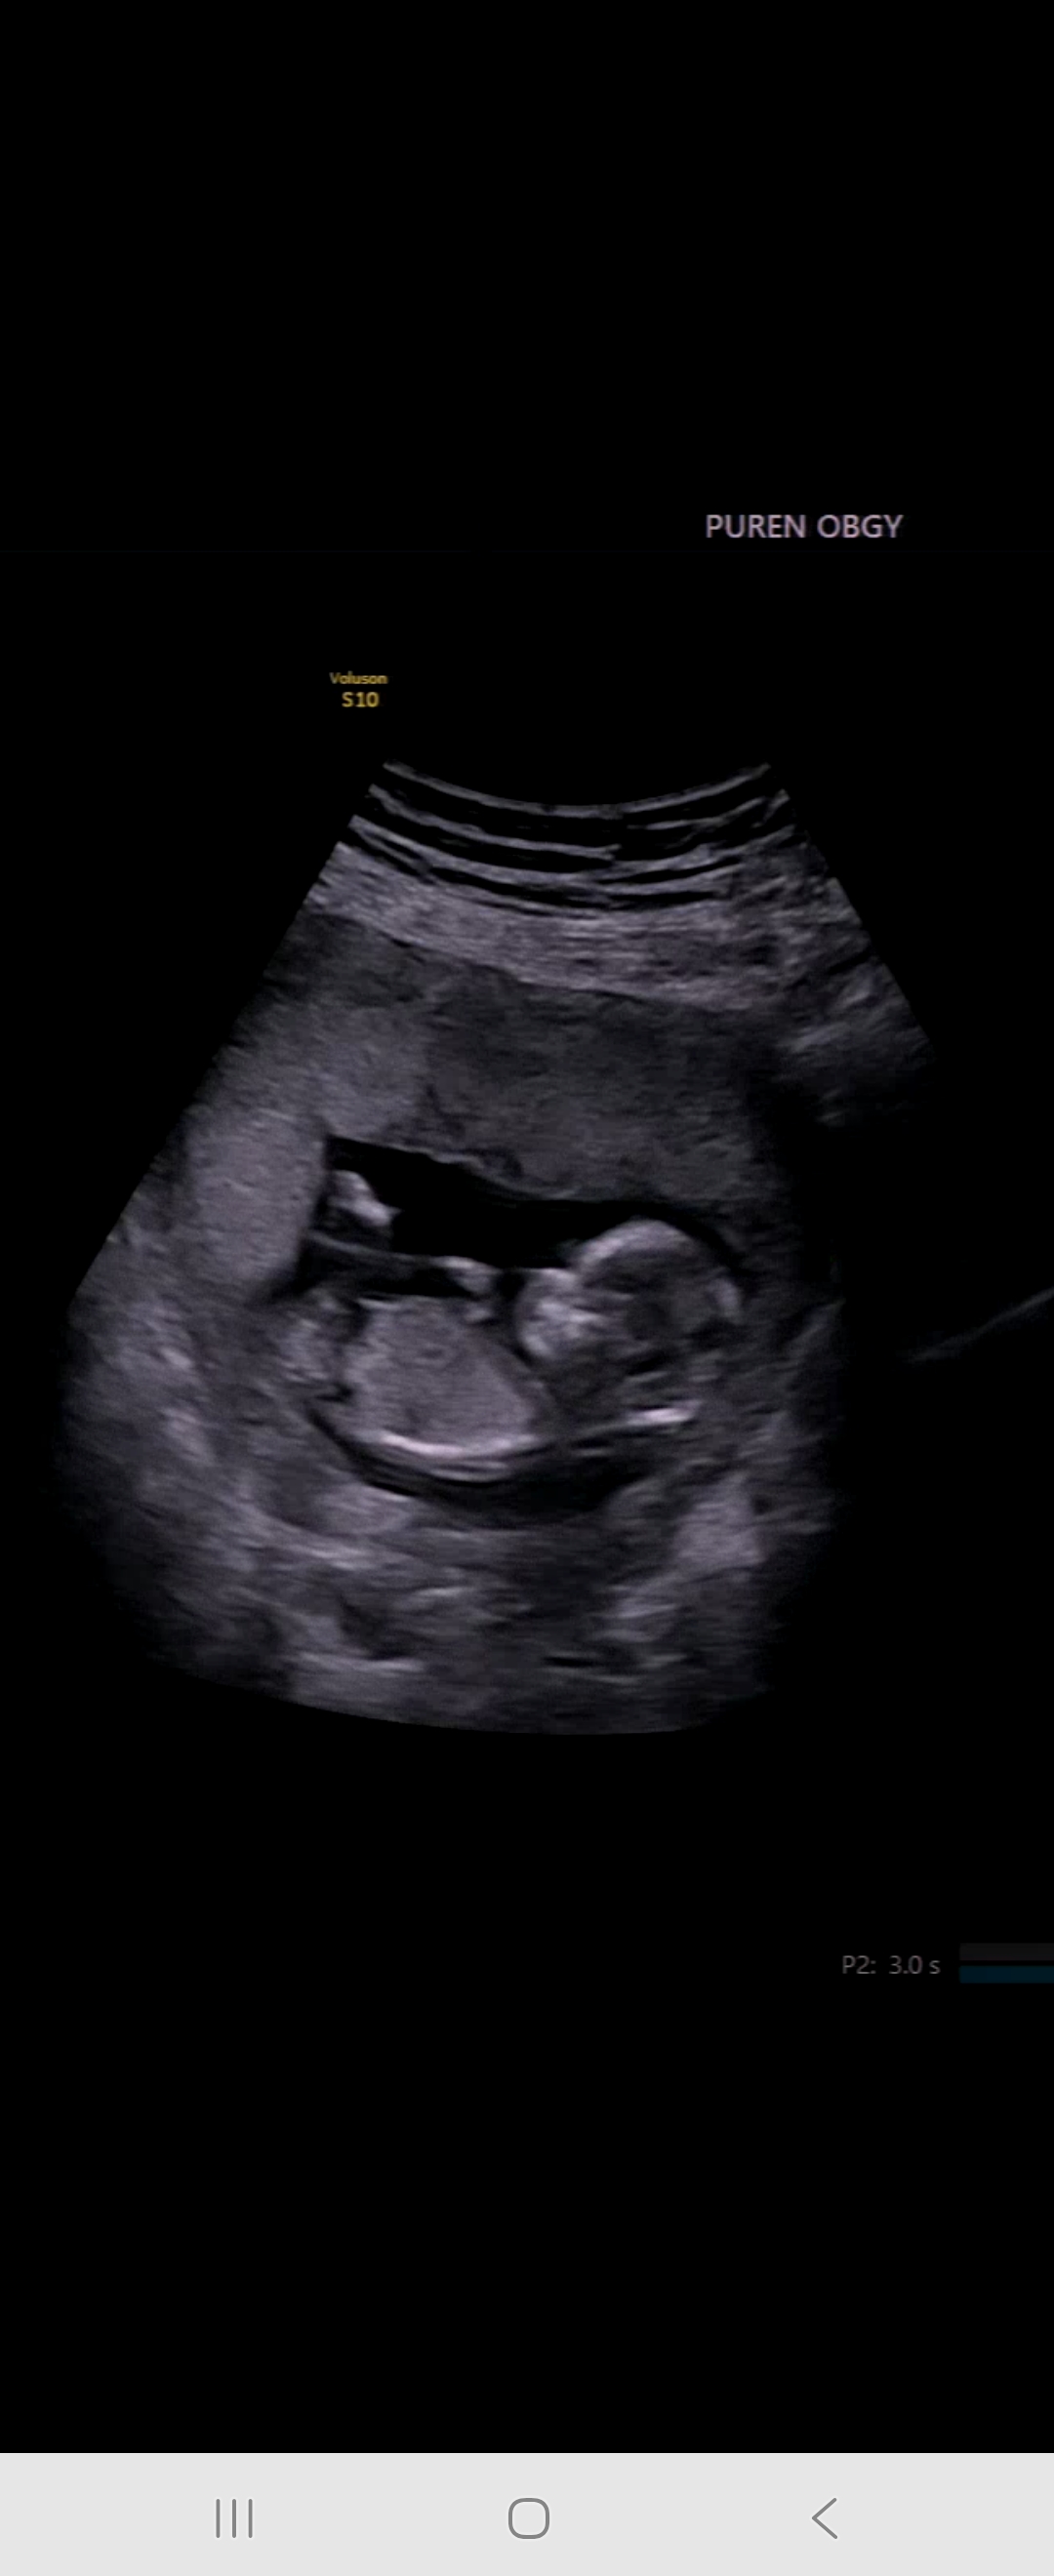

성별맞춰주세요!

성별이너무궁금합니다..ㅠ